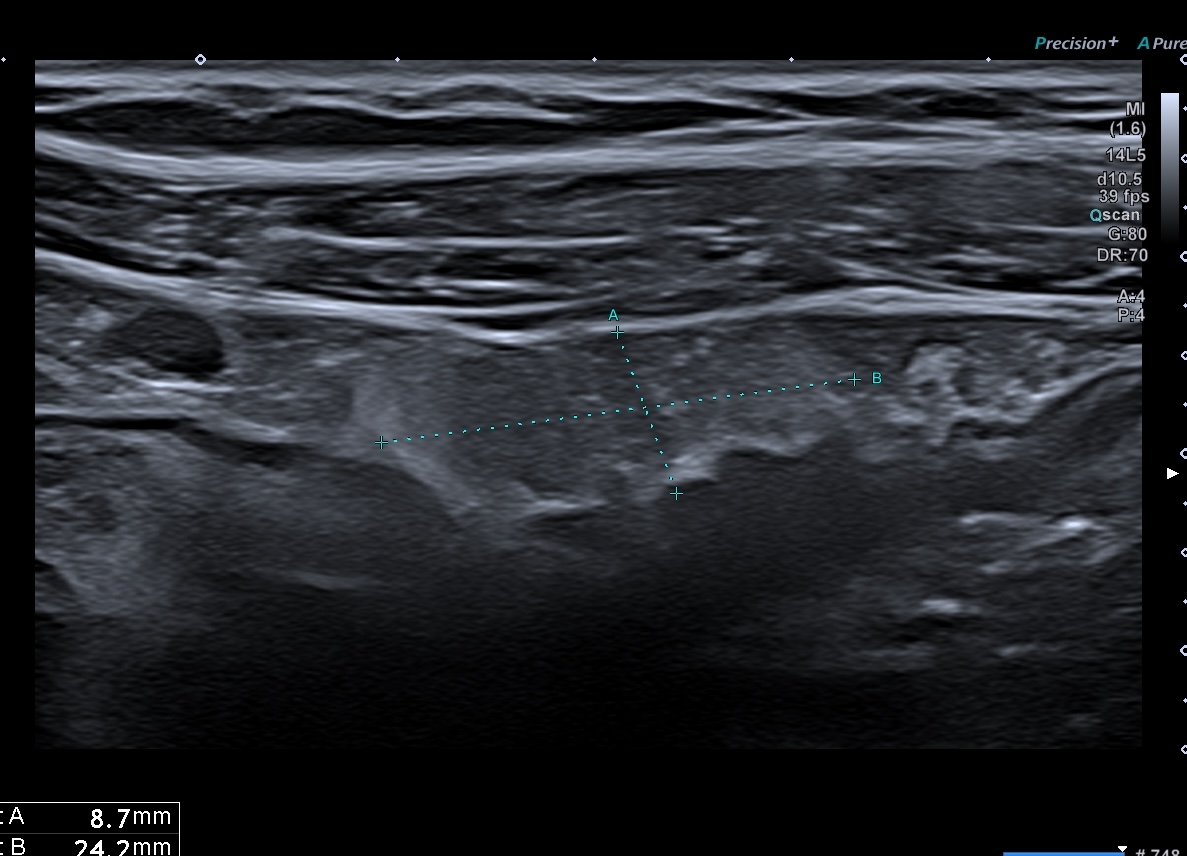

C'est la forme chronique de l'inflammation de la graisse, l'inflammation devient scléreuse, figée arrondie, plus hypoéchogène

- attraction de la séreuse en profondeur qui prend un aspect spiculé

- plus hypoéchogène

- Déformant la paroi localement

Sclérolipomatose antérieure iléon, graisse hypo échogène paroi Limberg 1 au maximum